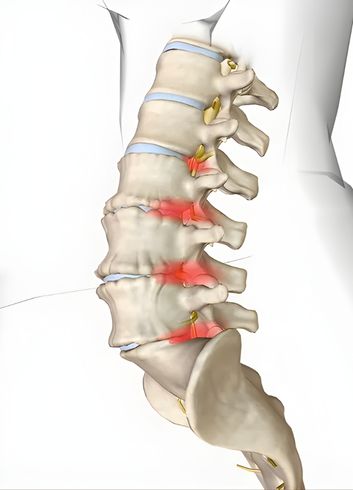

Esse processo de desgaste começa silenciosamente. O disco, que funciona como um amortecedor entre as vértebras, começa a desidratar e a perder sua elasticidade. Isso pode levar a uma instabilidade na coluna ou diminuir o espaço por onde passam os nervos. Embora muitas pessoas com degeneração discal não sintam absolutamente nada, em alguns casos, esse desgaste pode evoluir para quadros de dor crônica, rigidez ou até facilitar o surgimento de hérnias de disco.